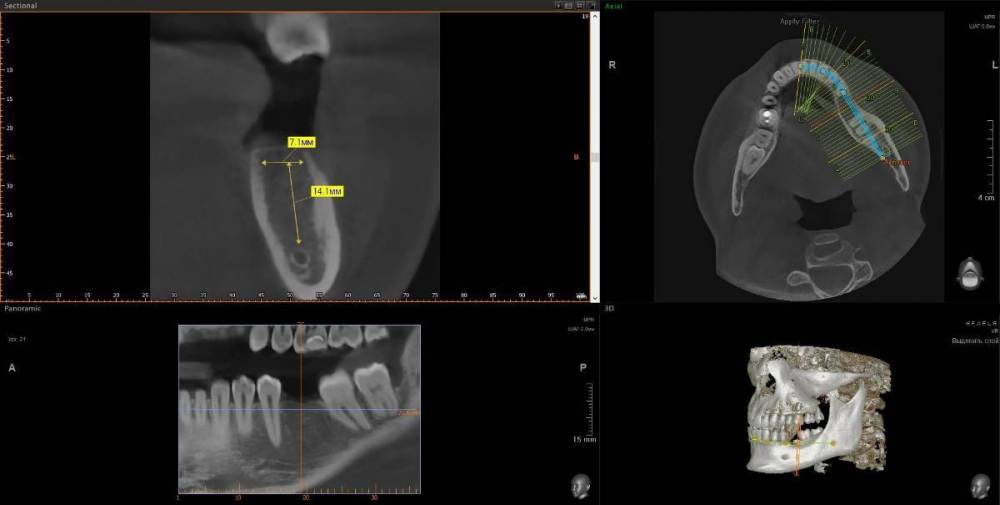

wladdX Опубликовано 17 января, 2024 Поделиться Опубликовано 17 января, 2024 (изменено) Думаю, что удаление зуба 46 - правильный выбор. Также имеется ретинированный зуб мудрости (48). С ним тоже лучше расстаться. У зуба 46 довольно широкая межкорневая перегородка, что даёт неплохие шансы на одномоментную установку имплантата. Зубы 18 и 28 (верхние зубы мудрости) наклонены щёчно, имеются кариозные полости недоступные для лечения - также на удаление Изменено 17 января, 2024 пользователем wladdX 2 Ссылка на комментарий

wladdX Опубликовано 18 января, 2024 Поделиться Опубликовано 18 января, 2024 Заочно трудно ответить на этот вопрос. Для начала удалить подвижную часть, тогда станет понятнее. 1 Ссылка на комментарий